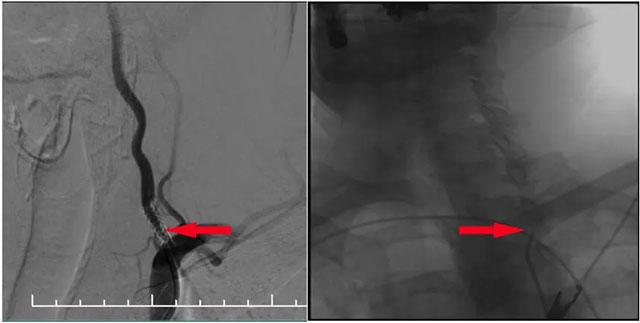

▲ DSA血管造影:左側(cè)椎動脈支架內(nèi)再狹窄

MR示雙側(cè)基底節(jié)區(qū)及右側(cè)頂葉凸面小梗塞(部分軟化灶形成)輕度腦白質(zhì)疏松,MR-tof 可見左側(cè)頸內(nèi)動脈巖骨段狹窄。DSA血管造影:左側(cè)椎動脈支架內(nèi)再狹窄,左側(cè)頸內(nèi)動脈造影見巖骨段遠端狹窄,右側(cè)大腦中動脈由左側(cè)頸內(nèi)部分代償,右側(cè)頸動脈造影提示右側(cè)頸內(nèi)動脈閉塞。